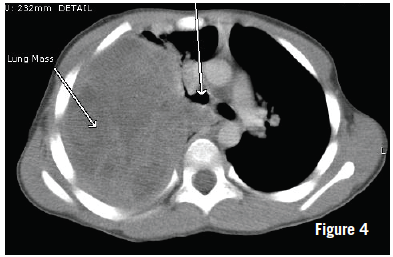

Computed tomography (CT) scans taken the next day showed a right pleural-based mass measuring 10.4 × 8.0 × 12.2 cm (Figure 4). The right lung showed significant lung volume loss and compression. No bony invasion or adenopathy was noted. There was a slight mediastinal shift. At this time, CT-guided biopsy was performed, the results of which later demonstrated spindle cell neoplasia but were insufficient for a definitive diagnosis. Core biopsy then was performed, the results of which demonstrated morphology consistent with type III pleuropulmonary blastoma (PPB).